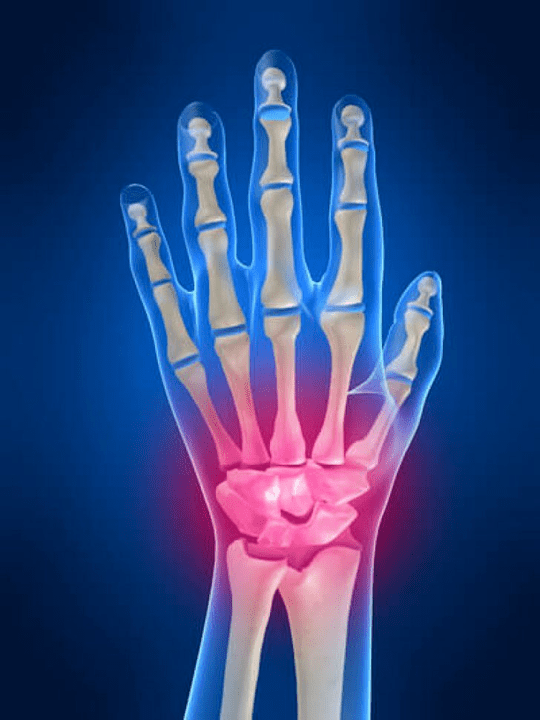

Joint painFinger is an indispensable sign of any joint disease in which the structural components of these joints are damaged.First of all, pain in the area of these joints can be associated with autoimmune diseasesSystemic red lust, rheumatoid arthritis, psoriasis, etc.) In which the immune factors cause damage to their own joint tissues.

The next main reason may beginpainIn the joints of the fingers, there may be wounds (Bruises, dislocations, fractures, ligaments).The pain in these joints can also be agitated by degenerative changes that occur in their joint tissues.This can often be observed with osteoarthritis.

The cause of the pain in the joints and fingers

The main sharing among the reasons for pain in the joints and fingers are occupied by mechanical trauma (Fracture, dislocated, bruises, etc.) and system autoimmune diseases (Rheumatoid arthritis, systemic lupus system, psoriasis, etc.).In addition to these causes, pain in the joints of the hand can cause diseases related to metabolic disorders (For example, gout, osteoarthritis).